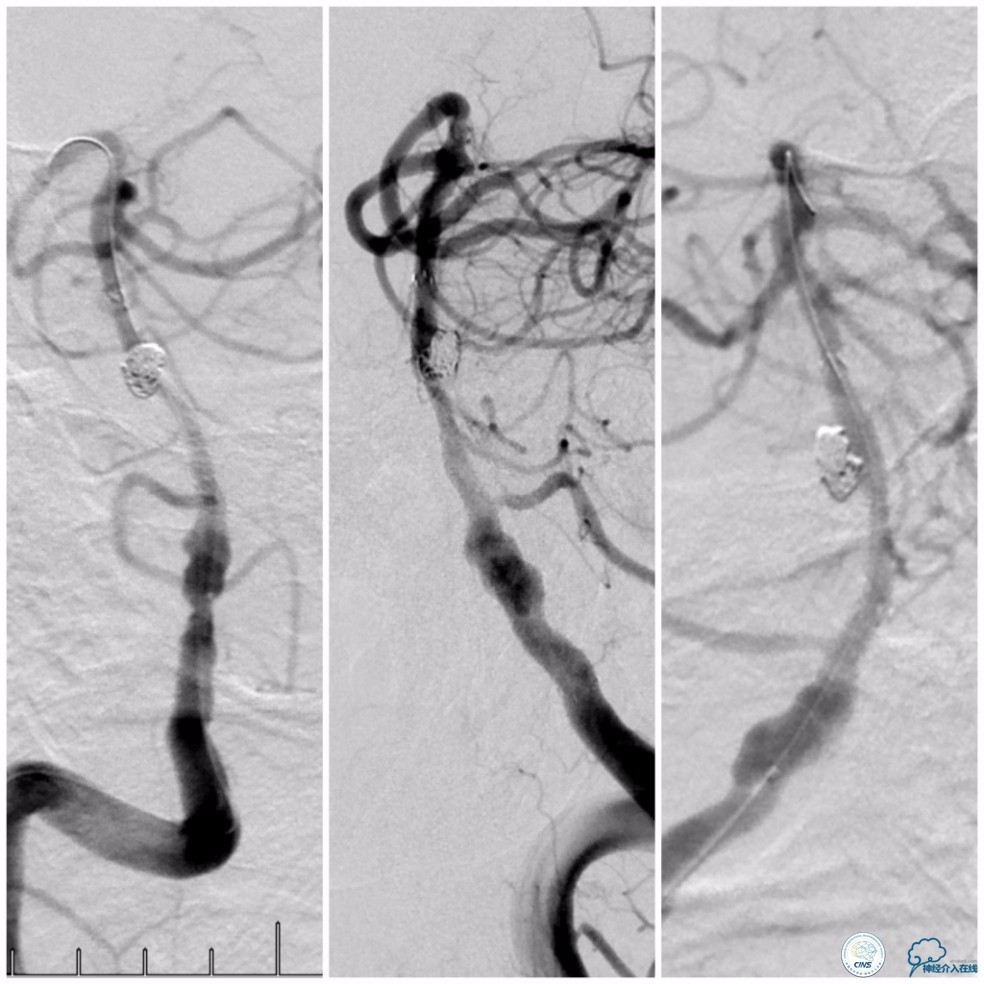

术前DSA:基底动脉中段狭窄,狭窄远端动脉瘤,右椎动脉优势,右椎V4段管壁不光滑(图7)。

图7

左椎动脉V3段以远未见显影(图8)。

图8

前循环未见明显向后循环代偿(图9)。

图9

Wingspan支架(3.0mm× 20mm)系统到位后,经5F导引导管放置Echelon-10微导管至动脉瘤腔内,释放Wingspan支架,进行动脉瘤栓塞(图11)。

图11

沿Echelon-10微导管依次推入EV3 PC-3-6-3D 3mm×6cm、QC-3-6-3D 3mm×6cm、QC-2-6-3D 2mm×6cm、QC 1.5-2-HELIX 1.5mm×2cm四个弹簧圈进入动脉瘤腔内。造影显示动脉瘤腔填塞致密(图12)。

图12

撤出Echelon-10微导管及5F导引导管。沿6F导引导管送入Select Plus微导管至基底动脉远端。经微导管送入Enterprise 4.5mm×28mm至右椎动脉V4段,两个支架重叠约2-3mm,完全覆盖右椎动脉V4段夹层(图13)。

图13